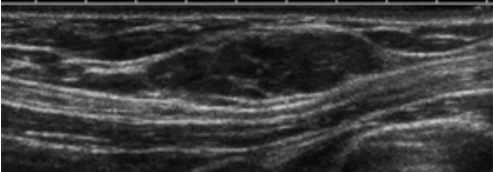

5. Đặc điểm hình ảnh và phương tiện khảo sát

Hầu hết tuyến vú được tìm thấy ngẫu nhiên trên chụp nhũ ảnh thường quy. Hình ảnh siêu âm cho thấy mô vú, không thể phân biệt với mô vú thông thường. Đôi khi, chụp cộng hưởng từ tuyến vú được thực hiện trong các trường hợp không điển hình. Biểu hiện bằng các đặc tính tín hiệu và ngấm thuốc tương tự như mô tuyến bình thường.